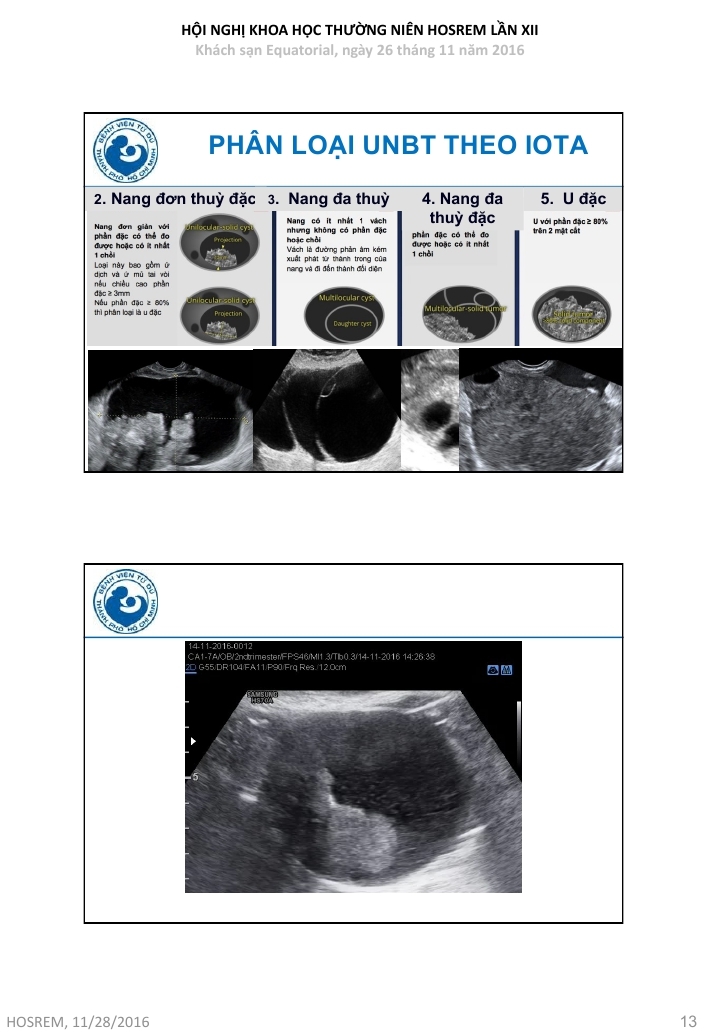

Ung thư buồng trứng  chẩn đoán và đánh giá nguy cơ ác tính theo IOTA

Từ khóa: Ung thư buồng trứng chẩn đoán và đánh giá nguy cơ ác tính theo IOTA